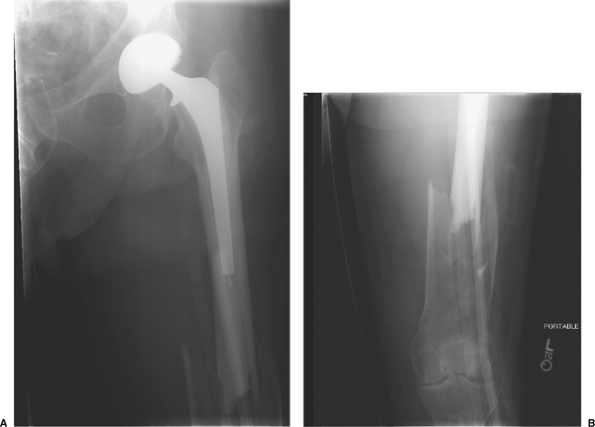

![]() |

|

Figure 45.5. Proximal AP (A) and distal AP (B) radiographs of a type III (distal fracture with a stable prosthesis).

complete, a standard lateral approach to the femur is performed on a

type III fracture with stable prosthesis (Fig. 45.5).